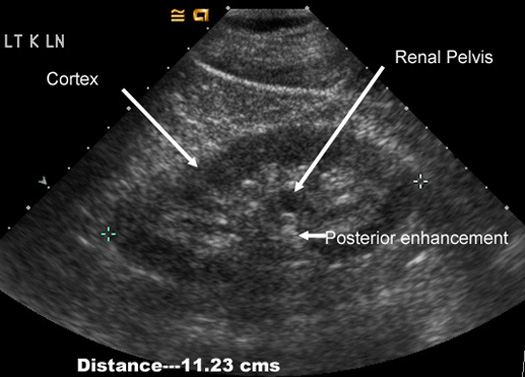

Normal Kidney in US

Measures 9-11 cm's

Has the same extent of echoes as liver

Cortex measures about 2.5 cm's

Central echoes are from fat surrounding renal pelvis.

Renal pelvis is filled with urine and is echo free. Note the posterior enhancement behind renal pelvis. |